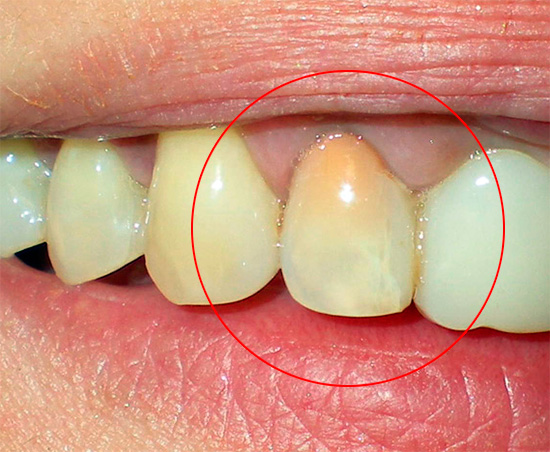

O diagnóstico por raio-X também é importante. Na pulpite fibrosa crônica, uma cavidade profunda de cárie, que quase sempre se comunica com a câmara pulpar, geralmente pode ser observada na radiografia de um dente doente. Às vezes, uma ligeira expansão do espaço periodontal (o espaço entre a raiz e o osso dos alvéolos nos quais está fixado) é fixada.

O diagnóstico diferencial de pulpite fibrosa crônica é realizado com cárie profunda, pulpite aguda e pulpite gangrenosa crônica. É com essas doenças que a pulpite fibrosa é mais semelhante.

A cárie profunda nunca se comunica com a polpa do dente, e a sondagem é dolorosa no fundo, e não em um ponto. A dor desaparece rapidamente com a eliminação do estímulo, em contraste com a pulpite fibrosa. As indicações de EDI para cárie profunda não são superiores a 20 μA e para pulpite fibrosa a partir de 35 μA.